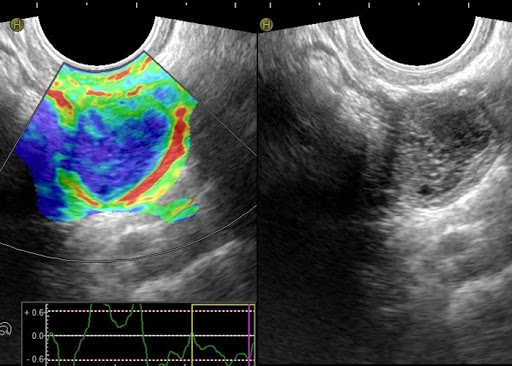

Цветной допплер

Позволяет выделять цветом характер кровотока в ROI (области интереса). Его применяют в сердечно - сосудистых исследованиях.

Кровяной поток, идущий от датчика, отображается синим цветом, к датчику – красным. Сине-зелено-желтым цветом выделяется турбулентный поток.

Эластография

Принятый за стандарт метод выявления опухоли. Данный метод построен на анализе отличий модулей Юнга (модулей продольной упругости).

С его помощью исследуют поверхностно расположенные органы и и получают качественные результаты исследования.